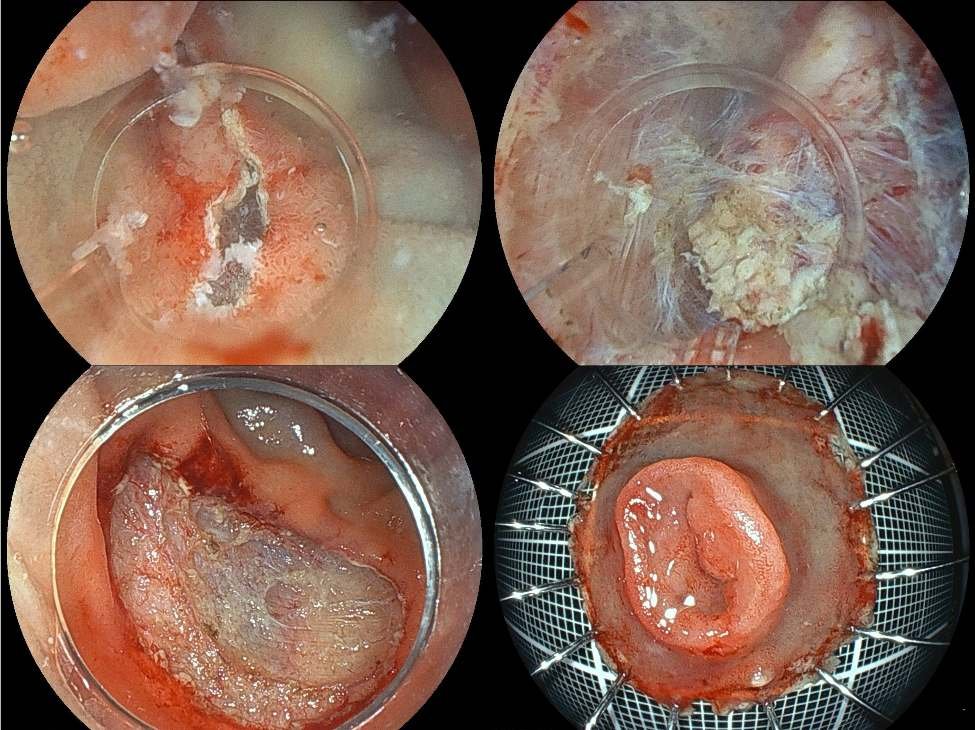

活检未发现癌细胞,但因病变持续增大且不能排除恶性可能,行内镜黏膜下剥离术(ESD)将病变完整切除(图B)。

图B